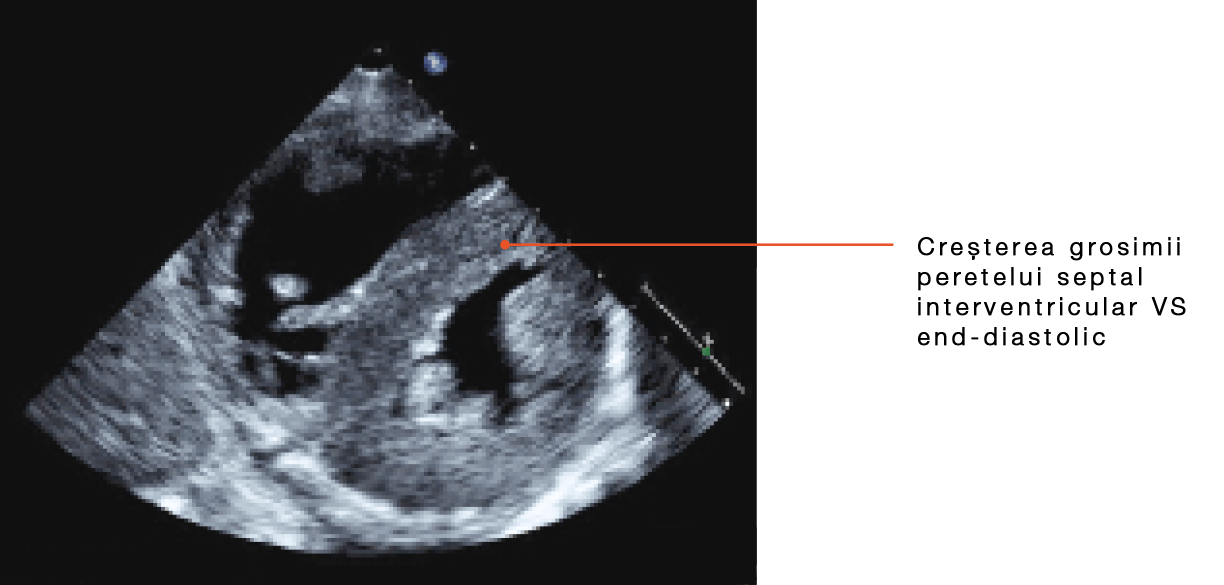

- În ATTR-CM, funcţia diastolică este afectată de depozitele de amiloid din miocard, care determină îngroşarea şi rigidizarea ventriculilor şi implicit debitului cardiac. Abia în stadiile mai avansate de evoluţie a ATTR-CM survine scăderea fracţiei de ejecţie8, 9

- Indiciile imagistice, precum reducerea strainului longitudinal cu sparing pe segmentul apical, pot creşte suspiciunea clinică1, 9